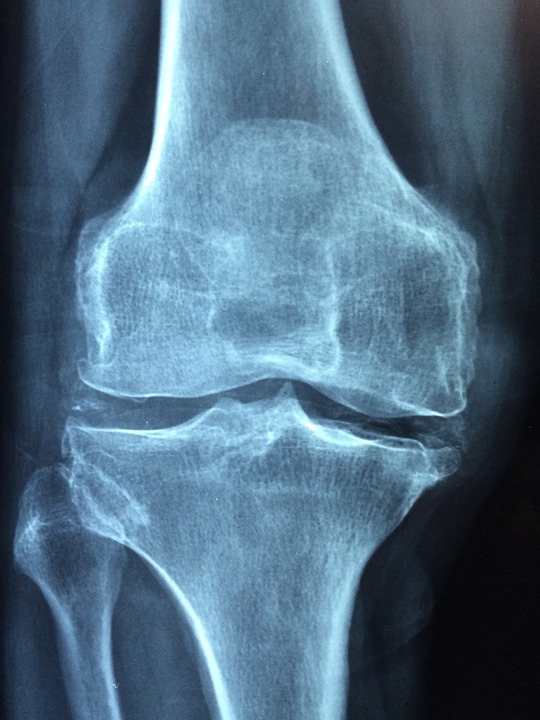

Osteoporose ist eine systemische Skeletterkrankung, die durch eine Abnahme der Knochenmasse und Veränderungen in der Mikroarchitektur des Knochens gekennzeichnet ist. Dadurch werden die Knochen schwach und brüchig. Die Krankheit tritt häufig im Alter auf, wobei Frauen nach den Wechseljahren besonders betroffen sind.